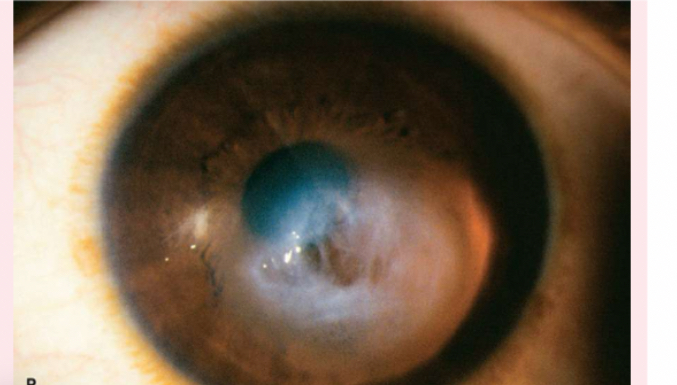

Nuclear cataracts

appear gray when seen with a flashlight; they appear as a black spot against the red reflex

Peripheral cataracts

look like gray spokes that point inward when seen with a flashlight; they look like black spokes that point inward against the red reflex when seen through an ophthalmoscope.